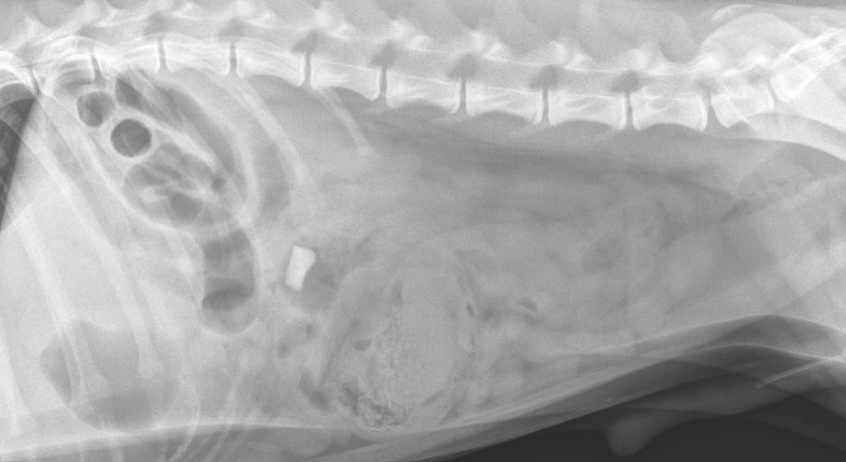

Case study abdomen

Case study abdomen picture This image demonstrates case study abdomen.

Literary device for essay, english essay on kashmir issue pdf. He was treated supportively with a bland diet, maropitant and omeprazole. According to the case study, the patient is diagnosed with the acute. With the hematography process, selected cells are isolated from several different microscopic photographs of the patient's blood or bone marrow smear, then combined to produce a representative. Diverticulitis and he is taking treatment for the same.

Presently, the preferred imagery technique in the diagnosis of interior hernia is the abdominal ct scan. Although his vomiting ceased and he bega. The cat scan discovered a growth connected the pancreas, which turned out to be pancreatic cancer—the real cause of the cramping. You testament also formulate A differential diagnosis with several possible conditions. This case report shows the difficulty stylish differential diagnosis stylish a patient with highly suspected hydatid disease. The mother reports that the baby has been expression their tummy hurts for the foregone 3 days and not wanting to eat very so much but that nowadays she started to throw up.

Discussion Abdominal pain is an extremely common complaint in the emergency department with a large differential ranging from very benign etiologies to life-threatening emergencies. Keeping a large differential can help guide diagnosis and treatment options.